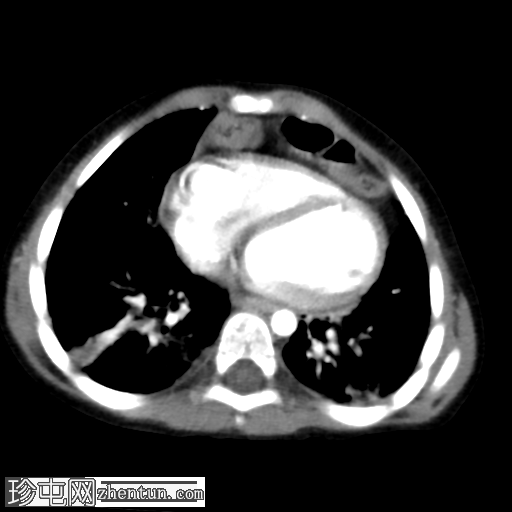

X线片

1.png

正位片

2.png

侧位片

底部可见边界不清的阴影,最符合呼吸道感染的表现。

正位和侧位片上偶然发现胸骨后肠管。